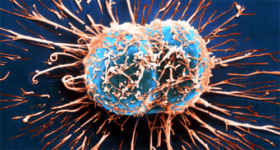

의학과 기술의 발달 덕분에, 자궁경부암 사망률은 많이 줄어들었고, 조기에 발견하는 것이 가능하게 되었다. 하지만 이것은 여전히 위험한 질병이다. 여성이라면 자궁경부암 의심 증상을 꼭 기억해둘 필요가 있고, 뭔가 위험한 느낌이 든다면 즉시 병원을 찾는 것이 좋다.

오늘은 피부암을 발견하는 방법을 알아보자. 피부암은 전 세계적으로 가장 광범위하게 나타나는 질병이다. 피부는 신체에서 가장 넓은 조직이며, 치명적인 해를 가할 수 있는 미생물이 몸속으로 들어오지 못하게 막는 역할을 한다. 또한 수분을 저장하고 체온을 조절한다.